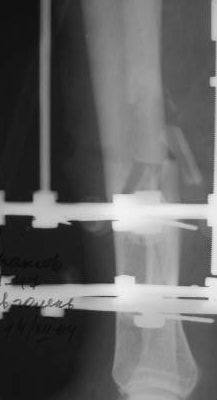

Когда уважаемый д-р Джолдас Кульджанов демонстрировал снимки закрытия раны на голени, у меня лечился больной по поводу открытого переломаголени в н/3 (3Б по Каплану), после вторичной обработки и стабилизации перелома АВФ, нанесены послабляющие разрезы кожи, оставался поперечный дефект кожи голени.

Решил использовать методику резиновой стяжки для закрытия дефекта. Рану разделил на две части . Одну часть стягивал с помощью скобок. Изготовил скобки из спиц 2мм. Скобками зацепил края раны, к скобкам привязал резиновые стяжки, которые фиксировал на деталях аппарата. Рана закрылась в течение 4х дней. Наложил вторичные швы.

Другую часть стягивал с помощью П-образных швов через резиновые трубки. В течение суток П-образные швы снял из-за угрозы прогрессирования некроза. На 4 день начал стягивать этот участок раны с помощью скобок и резиновой стяжки. Рана закрылась через 3 дня, наложил вторичные швы на этот участок. Метод понравился. Возникли вопросы.